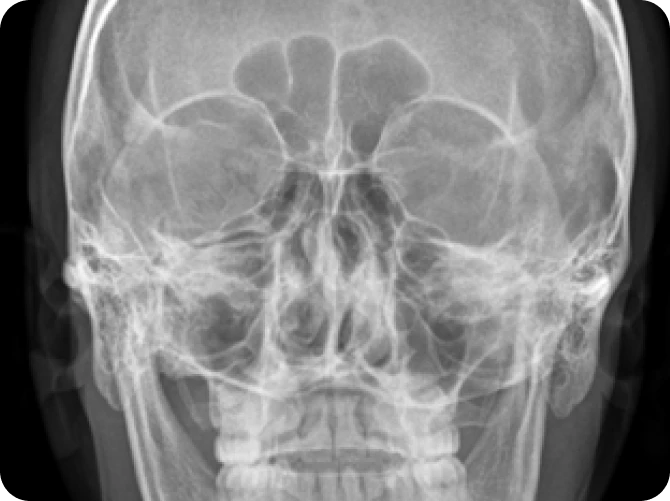

엑스레이

비중격의 휘어짐이나 코의 구조적 이상 확인